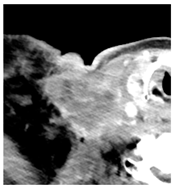

| 2 | 0–25 | 1564 | ![]() Axial CT image shows a partly necrotic tumor in the right neck. | ![]() Axial CT image obtained 18 days after injection shows the NBTXR3 nanoparticles (arrows) in the tumor. |